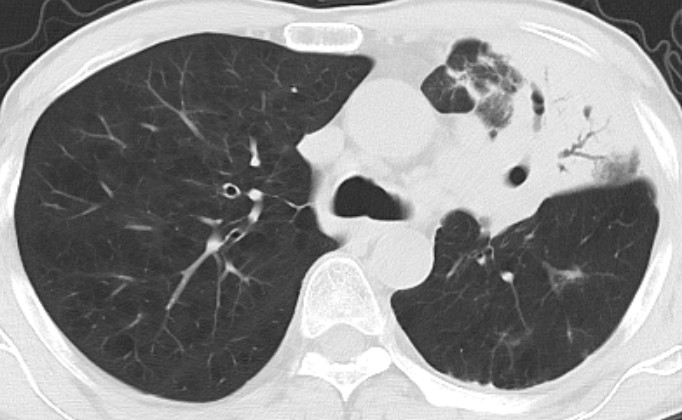

“我以为这次挺不过去了……”61岁的杨先生躺在病床上,高烧39℃、呼吸困难,左肺已被严重感染。从乡镇诊所到三甲医院,一场由普通感冒引发的“生死拉锯战”,在贵州航天医院呼吸与危重症医学科医护团队的守护下,最终康复出院。 【一场“小感冒”背后的危机】 杨先生因患有慢性阻塞性肺病,反复出现咳嗽、咳痰及气促症状多年。2025年初春,他因感冒出现咳嗽、气促等症状时并未在意,自行在诊所购买药物治疗。然而病情迅速恶化,十多天后,他高热至39℃,持续不退,伴有呼吸困难及明显胸痛症状,在当地医院诊治疗效欠佳,医院数次下达病危。家人随即将他转至贵州航天医院呼吸与危重症医学科治疗。 【多学科联手“拆弹”】 入院后,呼吸与危重症医学科医疗团队为患者进行了详细检查,胸部CT显示患者的左上肺严重感染、肺实变,血气分析提示呼吸衰竭,需要持续高流量湿化治疗才能维持氧饱和度。呼吸团队进一步行床旁气管镜检查,在患者的肺泡灌洗液中找到热带念珠菌、白色念珠菌、克柔念珠菌等多重真菌感染。面对这种复杂的感染情况,让治疗难度陡增。呼吸与危重症医学科的医生们迅速组织多学科会诊,制定了针对性的治疗方案,终于控制住了病情,患者持续十多日的高热终于退去,复查胸部CT肺部感染较入院时有所吸收,患者的胸痛、气促等症状明显改善。最终,在医护人员二十余天的不懈努力下,患者终于康复出院。 2025年3月10日CT显示 2025年4月9日CT显示 【二十天,见证生命奇迹】 在近二十天的治疗中,患者不仅得到了专业的医疗救治,更感受到了家人般的关怀。医护人员日夜守护,护理团队更以微笑与鼓励为他驱散病痛的阴霾。 医患同心,温暖永续 如今,患者已康复出院。他在感谢信中写道:“是你们精湛的医术让我起死回生,是你们温情的护理让我体会到家的温暖”。 这封感谢信的背后,镌刻着呼吸与危重症医学科团队日复一日的坚守——他们以精湛医术为矛,以仁爱之心为盾,为患者筑起坚不可摧的生命防线。 呼吸与危重症医学科专家简介 廖江荣 国务院政府特殊津贴专家、二级教授、民建遵义市委委员、民建遵义市委直属三支部主委、主任医师、贵州航天医院院长 学术任职: 亚洲冷冻治疗学会副主席 第二届中国医药教育协会介入微创专业委员会呼吸分会副主任委员 中国抗癌协会肿瘤微创治疗专业委员会常务委员 中国防痨协会结核病转化医学专业分会常务委员 第一届中国人体健康科技促进会呼吸介入专委会常务委员 中国医疗保健国际交流促进会结核病学分会第三届委员会常务委员 中国抗癌协会肿瘤微创治疗专业委员会粒子治疗学组第四届委员会委员 中国结核病防治综合质量控制专家指导委员会委员 “西部呼吸介入联盟”副理事长 专业擅长: 呼吸系统(肺)疑难病的诊断及危重病的抢救,呼吸系统(肺)感染性、疑难性疾病介入快速诊断(ROSE),尤其在肺癌、肺小结节早期诊断,肺癌微创综合靶向治疗,难治性、复治性、重症肺结核诊疗,硬质支气管下复杂性气道狭窄诊治,纤支镜介入治疗气道肿瘤、结核、气道狭窄(球囊扩张、支架植入、高频电刀、氩气刀、冷冻、灌洗、注药、微波消融),间质性肺疾病的诊疗上具有极高水平;带领团队勇于创新,在贵州省率先开展多项新技术、新疗法,如CT引导下及纤支镜下I125粒子植入及CT引导下微波、冷冻消融介入治疗肺癌等多项新技术,带动了贵州省肺部疾病的介入治疗水平提高。 唐永江 四川大学华西医院呼吸与危重症医学科副主任医师、呼吸危重症医疗组长、香港中文大学博士、美国康奈尔大学访问学者、贵州航天医院呼吸与危重症医学科学科带头人 主要从事呼吸危重症(特别是呼吸重症感染)的临床及科研工作。 PCCM专培结业医师 中华医学会呼吸病学分会呼吸危重症学组秘书 中华医学会呼吸病学分会ECMO工作组成员 四川省医学会呼吸病学专委会介入学组委员兼秘书 发表文章20余篇,主持及参与多项国家自然科学基金及省卫健委基金。 蒋 婷 中共党员,呼吸、感染党支部书记,呼吸与危重症医学科总负责人,副主任医师 专业擅长:从医20余年,在呼吸系统疾病、介入呼吸病学、肺部结核、肺部肿瘤等方面具有丰富的临床经验和专业技能,尤其是慢性阻塞性肺疾病、支气管扩张、肺结核、耐药肺结核、肺癌、胸腔积液等肺部疾病的诊治、微创介入、危重病患者抢救。 现任中国防痨协会人兽共患结核病专业分会委员,中国女医师协会第一届介入专业委员会委员,贵州省基层呼吸疾病防治联盟-间质性肺疾病联盟委员,贵州省防痨协会第七届理事会理事,贵州省中西医结合学会呼吸专业委员介入呼吸病学组委员,贵州省遵义市中医药学会中西医结合肺病(呼吸)分会副主任委员,贵州省遵义市中医药学会中医肿瘤专业委员会常委;发表论文数篇,参与并主持多项科研项目。 李桂凤 中共党员,呼吸与危重症医学科三病区主任,副主任医师 专业擅长:从事呼吸系统疾病、结核病学、介入呼吸病学、肿瘤综合治疗、呼吸康复等临床工作20余年,擅长呼吸内科常见病、多发病及疑难重症危重病症的诊治,尤其对重症疑难结核及耐药结核病、介入治疗(肺)呼吸系统疾病、呼吸危重病抢救等方面具有较高诊疗水平。 中国防痨协会非结核病专业委员会委员,贵州省中西医结合学会第六届呼吸专业委员会委员,贵州省康复学会睡眠障碍康复专业委员会委员,遵义市呼吸内科医疗质量控制中心委员,遵义市落实民生实事结核病筛查阅片专家组成员;主持及参与实用新型专利3项。 周裕祥 中共党员,呼吸与危重症医学科四病区主任,副主任医师 专业擅长:经皮肺介入、经血管介入诊疗技术。 贵州省中西医结合学会呼吸专业委员会介入呼吸病学组常务委员,中国医师协会呼吸医师分会介入呼吸病学工作委员会呼吸病血管介入学组委员,贵州省中西医结合学会呼吸学分会委员,遵义市医学会放射肿瘤治疗学分会委员,中国医药教育协会介入微创呼吸分会委员,北京健康促进会中青年专家委员会胸部疾病精准活检分委会委员;曾赴重庆医科大学RICU、珠海市人民医院介入科进修学习。 杨 芳 中共党员,呼吸与危重症医学科内镜中心主任,副主任医师 专业擅长:从事临床工作约20年,对呼吸危重病的救治有独到的见解,尤其擅长呼吸系统疾病的介入诊疗,对呼吸内镜下的诊治及经皮肺穿刺诊疗技术具有丰富的临床经验。 亚洲冷冻治疗学会委员,中国医药教育协会介入微创呼吸分会委员,西南结核病医院联盟第二届委员会秘书/委员,贵州省中西医结合学会第六届呼吸科专业委员会委员,贵州省中西医结合学会呼吸专业委员会介入呼吸病学组秘书,贵州省中西医结合学会呼吸专业委员会基层康复学组副组长,贵州水利电力医学科学技术会高原医学分会委员,遵义市中医院学会中西医结合肺病(呼吸)分会秘书/常务委员,遵义市医学会肿瘤学分会(第二届)委员,遵义市医学会放射肿瘤治疗学分会第二届委员;主持及参与科研课题多项,参编著作《呼吸内镜操作技术规范》、《介入结核病学》,发表论文数篇。 呼吸与危重症医学科简介 贵州航天医院呼吸与危重症医学科以呼吸危重症和介入呼吸病学为强力推手,以肺部感染性疾病及肺癌、肺小结节的早期精准诊疗、慢性呼吸疾病康复治疗为特色,以人才团队建设为核心的科室发展模式,现已成为贵州省内呼吸疾病治疗规模最大、诊疗项目最全的呼吸疾病品牌科室。是贵州省医学重点学科、临床医学重点专科建设单位,遵义市首批呼吸重点学科、重点专科建设单位。是国家卫健委能力建设和继续教育肿瘤微创介入建设中心、贵州省县级医院微创介入培训中心、遵义市呼吸疾病临床医学中心。是国家呼吸医疗质量控制与管理哨点医院、遵义市呼吸内科专业医疗质量控制中心。是中国医药教育协会介入微创呼吸分会呼吸介入技术培训中心单位;国家卫健委海医会呼吸分会ROSE专委会“诊断性介入肺脏病学快速现场评价”培训基地;中国肺癌防治联盟“贵州航天医院肺结节诊治”分中心,中国人体健康科技促进会呼吸介入技术培训基地,贵州省中西医结合会呼吸学分会呼吸介入专委会主委单位。 基本情况 平均每年开展气管镜诊疗约4000例,经皮肺穿刺介入诊疗近千例,开展的项目包括经支气管镜(软、硬)下冷冻、氩气刀、高频电刀、球囊扩张、支架置入、超声内镜诊疗等气道介入诊疗技术,经皮肺穿刺活检及肿瘤消融术(微波、冷冻)、ROSE技术、内科胸腔镜诊疗及经血管介入诊疗技术,且多项呼吸介入诊疗技术在省内处于领先水平。 诊疗范围 专科擅长:致力于呼吸系统感染性、疑难性疾病的介入快速精准诊疗;肺癌与肺小结节早期精准诊疗水平项目提升。擅长呼吸系统(肺)疑难病的诊断及危重病的救治,尤其是肺癌、肺小结节的早期诊断,肺癌综合靶向治疗,肺结核综合诊疗等肺部疾病的介入诊疗在贵州省内处于前沿水平。 咨询热线 (一)呼吸与危重症医学科一病区 医生办公室:27677317 护士站:28614217 (二)呼吸与危重症医学科二病区 医生办公室:28691274 护士站:28690442 (三)呼吸与危重症医学科三病区 医生办公室:28692417 护士站:28690461 (四)呼吸与危重症医学科四病区 医生办公室:28616402、27677582 护士站:28614987、27677862